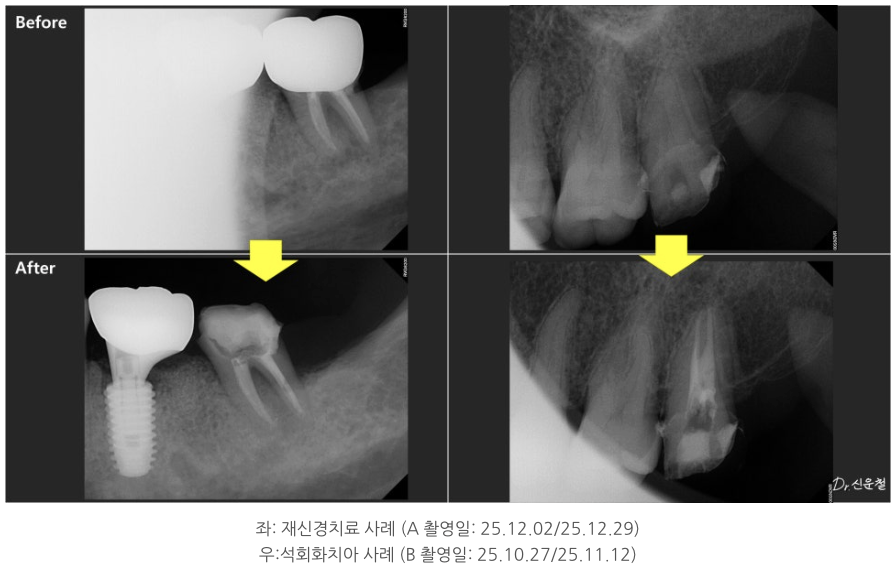

석회화된 치아, 정말 방법이 없을까?

실제 내원 사례 중에는

이미 신경치료를 받은 어금니에서

잇몸이 다시 붓고 고름이 차

발치 진단을 받고 오신 분도 계셨습니다.

또 다른 분은

“신경치료가 어렵다”는 설명을 듣고

의뢰로 내원하신 경우였습니다.

이 치아의 특징은 치아 안쪽 신경이 지나가는 길이

오랜 시간에 걸쳐 점점 막혀 있던 상태,

즉 석회화였습니다.

중요한 건 ‘과거 치료’가 아니라 ‘지금 상태’

이 두 경우 모두에서

치료 시작 전 가장 중요했던 기준은

과거에 어떤 치료를 받았는지가 아니라,

- 지금 이 치아 안쪽에 다시 접근할 수 있는 여지가 있는지였습니다.

치아 안쪽을 직접 확인하면서

남아 있는 길이 있는지

다시 정리가 가능한 상태인지 를 기준으로 판단했고, 그 결과

두 경우 모두 발치 대신 신경치료를 진행할 수 있었습니다.